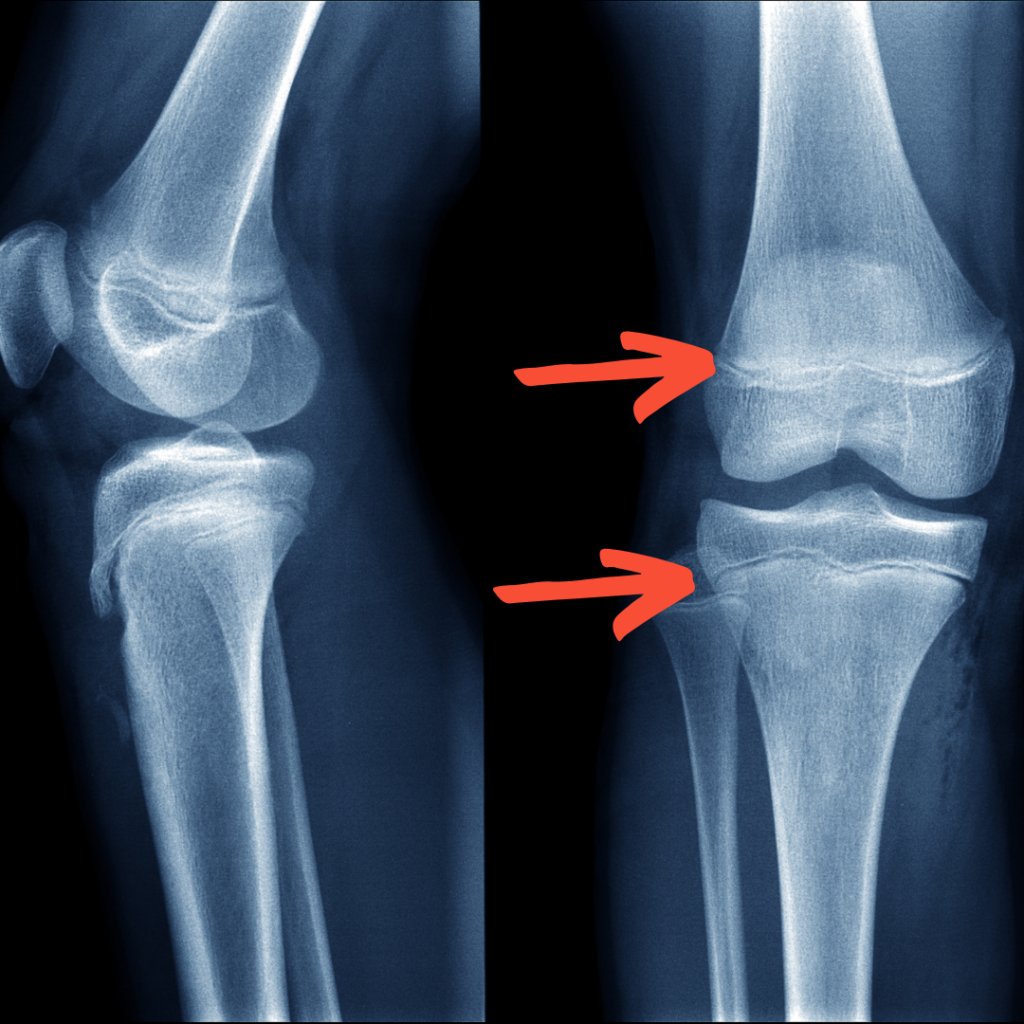

成長期の子供の骨は伸びていきます。そのため、身体中の骨には伸びるための伸びしろがあります。その伸びしろの部分を骨端線と呼びます。

シーバー病はかかとの骨ですが、すねの骨や太ももの骨にも骨端線があります。この部分は構造的にその他の部分と比べて弱く、強い力がかかると容易に折れてしまいます。(写真はひざの骨)